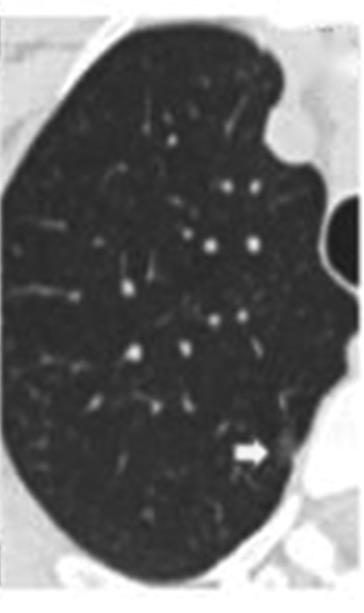

• 纯磨玻璃结节肺腺癌CT征象与其浸润程度的相关性分析及预测模型构建

2023, 48(4):423-429. DOI: 10.13406/j.cnki.cyxb.003200

摘要 (138) HTML (44) PDF 1.10 M (286) 评论 (0) 收藏

摘要:目的 探究纯磨玻璃结节(pure ground-glass nodule,pGGN)肺腺癌计算机断层扫描(computed tomography,CT)征象与其浸润程度的相关性,建立CT征象与浸润程度的预测模型。方法 回顾性分析424例经手术切除、病理活检证实且胸部CT表现为pGGN的肺腺癌患者临床资料及CT征象,根据病理活检结果分为非典型腺瘤样增生、原位腺癌、微浸润腺癌和浸润性腺癌4组,对组间差异采用卡方检验或Fisher确切概率法进行统计分析。对有统计学意义的结果,使用怀卡托智能分析环境(Waikato environment for knowledge analysis,WeKa)中的6种学习算法进行预测模型构建,并验证准确性,挑选出最适用于本研究的预测模型。结果 4组间在结节直径、结节密度值上的差异具有统计学意义(P<0.001),对应的直径平均值分别为6.90、8.65、10.71、14.56 mm,对应的密度平均值分别为-633.16、-543.04、-401.03、-322.94 HU,随着病灶的浸润程度加重,结节的直径及密度值呈现明显的上升趋势。4组间在结节边界、分叶、毛刺、血管穿行、胸膜凹陷、空气支气管征、空泡征等的差异具有统计学意义(P<0.05),而结节的生长位置,年龄、吸烟史、直系亲属肺癌家族史等差异无统计学意义(P>0.05)。随机森林算法所构建的模型预测准确率为76.42%~79.72%,Kappa系数为0.597~0.670,受试者工作特征(receiver operating characteristic,ROC)曲线下面积均大于0.9,在误差指标中表现最优,是最适合于本研究的预测模型。结论 pGGN的不同CT征象与其浸润程度密切相关,可以用于建立预测模型。基于随机森林算法所建模型,在有创干预前早期快速识别pGGN浸润程度的平均准确率为78.07%,准确度最高,对肺癌预测具有潜在应用价值。